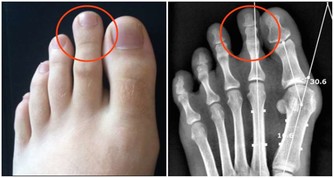

*****3、冠心病*****

根據數據顯示,近年冠心病的年輕趨勢越來越明顯。但是由於早期冠狀動脈粥樣硬化的症狀不明顯,常常會被人所忽視。

殊不知,如若冠狀動脈粥樣斑塊破裂,發生心肌缺血,就會引發致死性心律失常,最終導致猝死。

那這類猝死到底有啥先兆呢?以下幾個症狀,需要警惕,及時去醫院治療:

①憋悶、心悸、眩暈;

②胸前區壓榨性疼痛、肋骨下疼痛、左胸部疼痛;

③出冷汗和失神等;